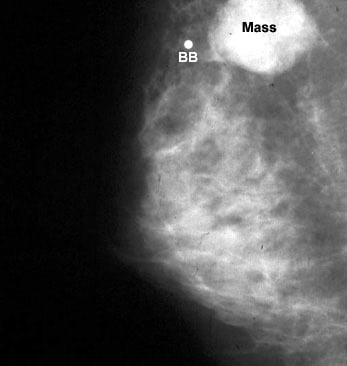

Mamografi (Altın Standart):

Spiküle Kitle: LR (+) > 20.0.